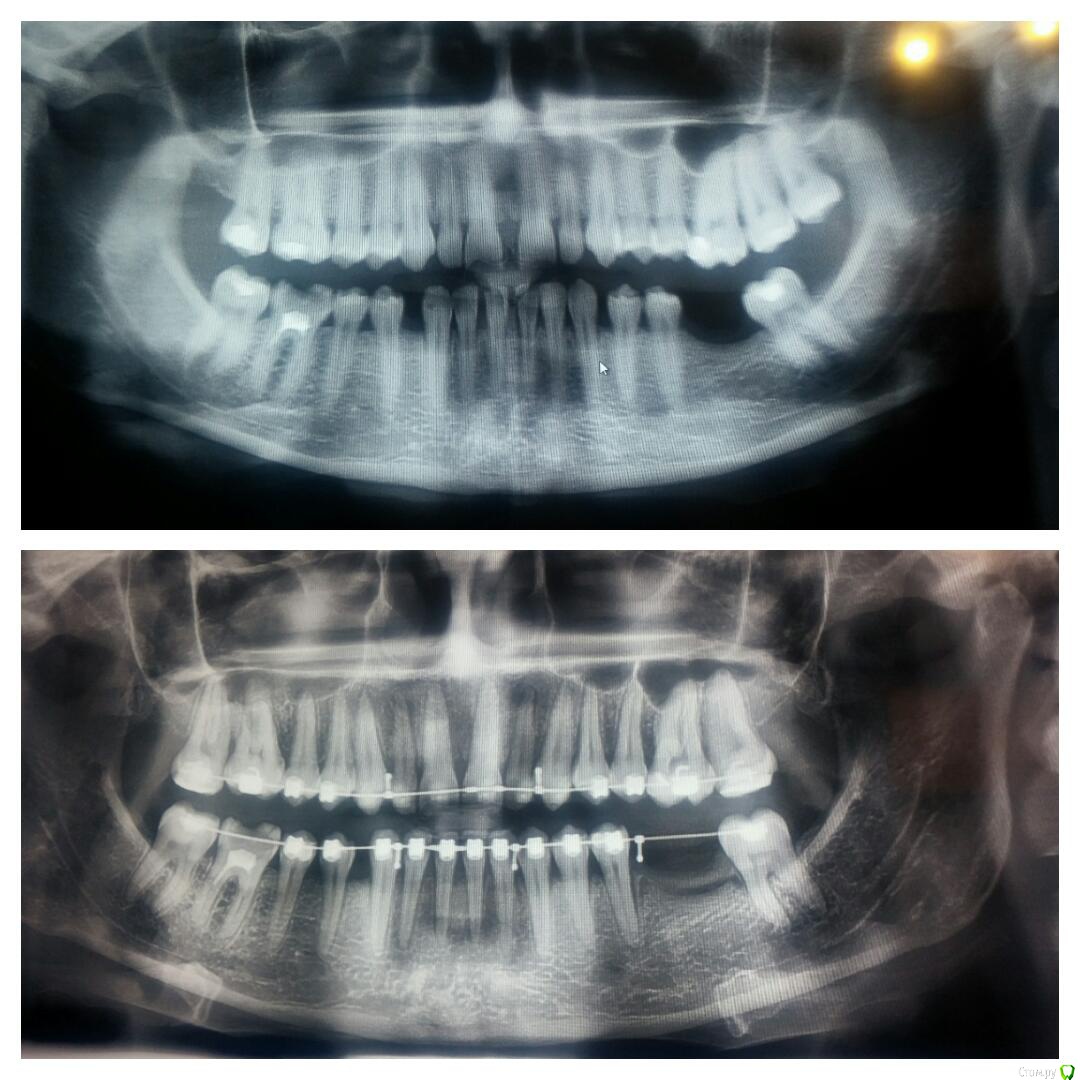

Елена Fy Опубликовано 14 августа, 2015 Поделиться Опубликовано 14 августа, 2015 (изменено) Носила брекеты 1.5 года, сняли месяц назад. Сразу сильно удивил наклон нч вовнутрь, да и верхней тоже. Ортодонт сказала, что это такой прикус и всë нормально. Сейчас ношу капы,но даже в них ВЧ давит на НЧ, есть дискомфорт передних зубов.До брекетов прикус больше устраивал, но смущали щели, вот и пришлось брекеты носить. Подумываю об исправлении прикуса капами.(опять затраты)Подскажите, пожалуйста, может я зря беспокоюсь и это действительно такой прикус? Изменено 14 августа, 2015 пользователем Елена Fy Ссылка на комментарий

Yana guapa Опубликовано 15 августа, 2015 Поделиться Опубликовано 15 августа, 2015 Сразу сильно удивил наклон нч вовнутрь, да и верхней тоже. Ортодонт сказала, что это такой прикус и всë нормально.жалобы на что? п.с. у вас и до лечения нижние зубы были завалены во внутрь. Ссылка на комментарий

Елена Fy Опубликовано 15 августа, 2015 Автор Поделиться Опубликовано 15 августа, 2015 жалобы на что? п.с. у вас и до лечения нижние зубы были завалены во внутрь.Возможно наклон и был, но не такой сильный. По вашему мнению этот прикус в пределах нормы? Меня он лично смущает(( Ссылка на комментарий

Yana guapa Опубликовано 15 августа, 2015 Поделиться Опубликовано 15 августа, 2015 Возможно наклон и был, но не такой сильный. По вашему мнению этот прикус в пределах нормы? Меня он лично смущает((Елена, Вы понимаете, положение и наклон нижних зубов ограничен размером "арки " верхней челюсти. если она у Вас сужена (а Вам в конце лечения именно такой наклон верхних зубов сделали), то и нижний зубной ряд будет сужен, "завален"У многих от природы такой наклон. если не беспокоит - оставляют так. . если есть жалобы - тогда уже исправляют Ссылка на комментарий